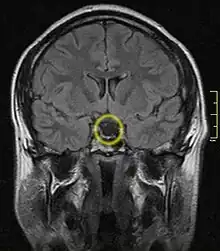

| Empty sella turcica on MRI as seen in severe cases of Sheehan's syndrome | |

MRI is useful in diagnosing Sheehan's syndrome since it examines the structure of the pituitary and may identify any anatomical damage.[4] MRI findings will vary based on how early or late in the disease process the test is being conducted. If an MRI is conducted early enough in the disease process the pituitary may appear larger than normal, and show changes that are consistent with damage from lack of blood supply.[15] Later in the disease process of this syndrome the damage imposed on the pituitary gland will cause it to shrink, and leave a partially empty or totally empty sella turcica on MRI.[7]